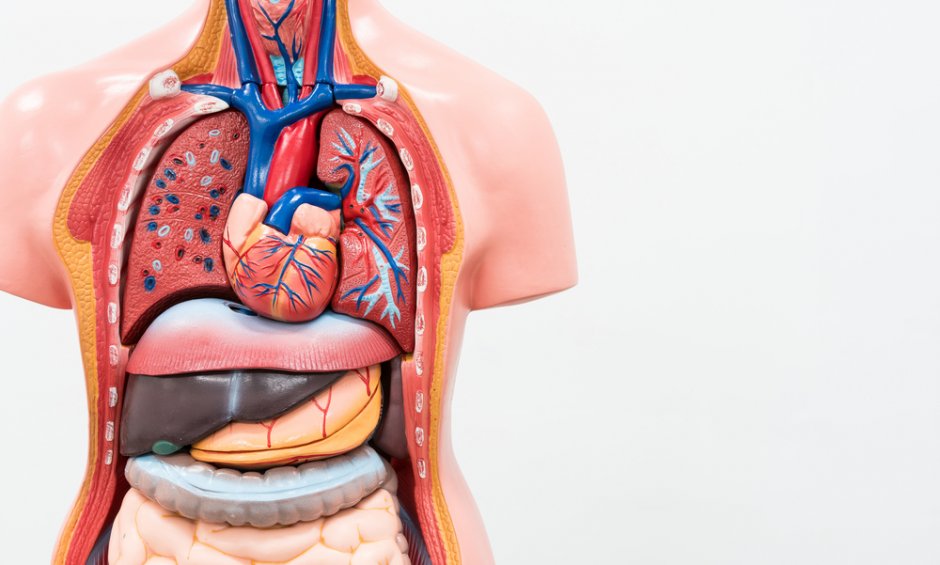

Τα σπλαχνικά αγγεία, όπως αλλωστε και το όνομά τους δηλώνει, εξασφαλίζουν την αιμάτωση του πεπτικού συστήματος – στομάχι και έντερο- και σημαντικών οργάνων όπως ήπαρ ,σπλήνας και τα νεφρά. Η καλή λειτουργία τους παίζει κρίσιμο ρόλο στην επαρκή οξυγόνωση και θρέψη των οργάνων μας, επιτρέποντας τη σωστή λειτουργία τους είναι δε κλειδί για την υγεία μας, την ποιότητα της ζωής μας και, σε πολλές περιπτώσεις, για την ίδια μας τη ζωή.

Η Προστασία των Σπλαχνικών Αγγείων εξασφαλίζει ποιότητα ζωής και μακροζωία!